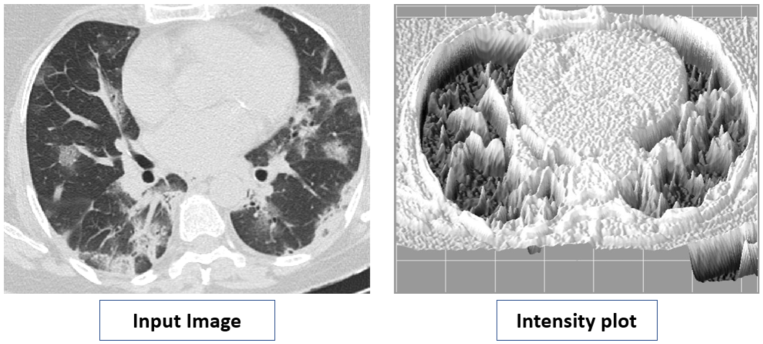

Thoracic radiology evaluations found high rates of ground-glass opacities and consolidations in COVID-19 patients. One can observe the ground-glass opacities (GGOs) together with consolidations in the CT-Scan of COVID-19 images. These regions are isolated with difference in shapes (left image in Fig. 8), which is captured by PDs associated to and . Moreover, these regions have unique shape in the intensity plot, see appearance of alps, saddle points in Fig. 8 (right image). These are recorded by PDs of Lower-star-filtration and .

Lower Star Filtration (LSF) captures key features about variation in intensities in an image. Local minimum and saddle points, in the intensity plot, are vital shape features (see Fig 11). These features are recorded using LSF. The birth time of a point in this PD is local minimum and death time is saddle point.